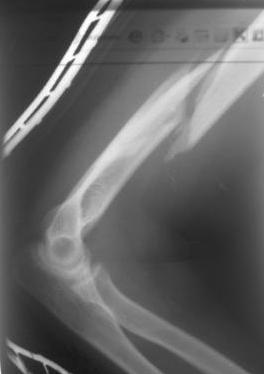

Перелом нестабильный, тактика - если позволяет сосояние больной, оперативное лечение. Как пример см. ниже, можно без скобы - стяжки с ЭПФ.

А вы не хотели поставить штифт... мы хотим штифтовать, единственный вопрос можно ли поставить антеградно или нет?

Уважаемый товарисч.Данный перелом можно вылечить антероградным, ретроградным штифтованием, пластиной, аппаратом внешней фиксации, вытяжением за локтевой отросток на шине ЦИТО. Учитывая наличие тяжелой ЧМТ предпочтение должно отдаваться минимальноинвазивной технике.

Качество паредставленных Вами рентгеновских снимков крайне низкое, что косвенно свидетельствует об общей культуре работы в Вашем отделении.